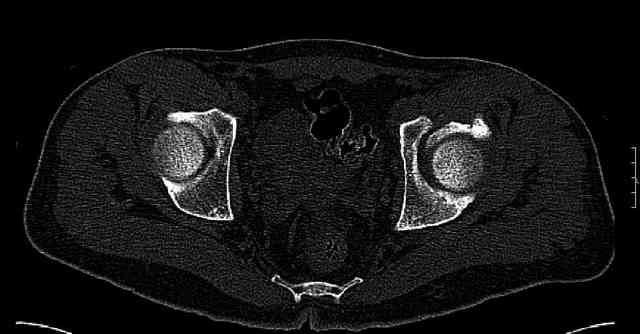

The joint is non-concentric as the head appears to be either "following the caudal segment", or the dome component is displaced from the tethered head... or so it seems... and he's young... so, many fracture surgeons would recommend reduction and fixation.

So we must decide preoperatively which part is the displaced segment?

It's difficult to know from these few selected images which component of the injury (was before and now) should be deemed the "soon to be mobile"

segment. It's my best guess that it is the caudal portion and there exists a healing fracture line somewhere thru the posterior column...one image

suggests it. If true, its early healing/union should be disrupted, and the resultant fragment mobility then allows accurate reduction.

Some more images. Does it help to guess which part of the acetabulum is displaced?

Normal appearing SI joints and a healed posterior column limb... my bet's on caudal segment displacement.